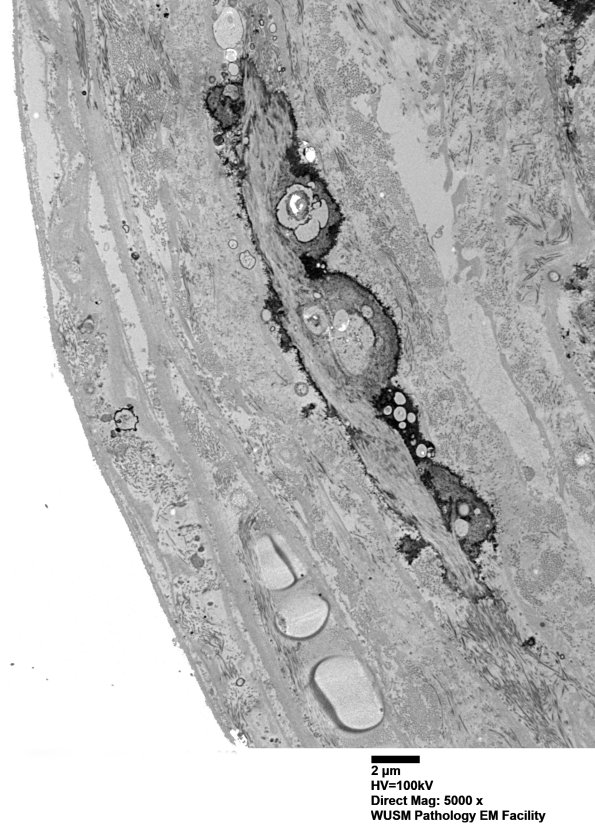

6B4-6 Additional images of perineurial calcification. Perineurial calcifications can be seen in normal individuals as a function of age and as a nonspecific feature of peripheral neuropathies. (electron micrographs)